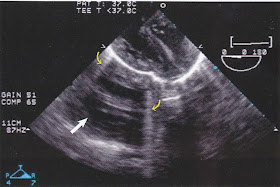

Echo artifacts

Five types of artifacts:

1) Mirror image artifact (Created by residual waves continuing to travel beyond the object of interest. Then, gets reflected back from interfaces beyond. These waves are once again reflected by the object giving rise to the second image.

2) Reverberation artifact

3) Side lobe artifact (Produced by radial vibration of piezo electric crystals, instead of the longitudinal vibrations of the main beam)

4) Grating lobes artifact (no image) occurs in array transducers (?)

5) Acoustic shadowing (occurs due to highly reflective interface such as calcification).

(All images are from TEE for congenital heart disease by Wong PC, Miller-Hance WC. Springer Verlog London. 2014.)